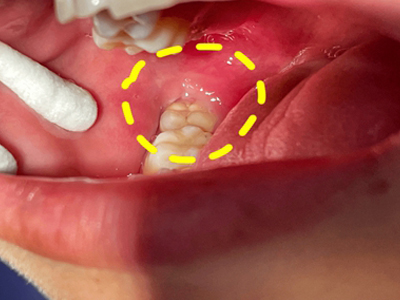

智齿冠周炎牙龈黏膜红肿图

智齿冠周炎患者症状为智齿邻近的牙龈和颊侧黏膜红肿、疼痛,口腔内腺体分泌增加,口水增多。牙齿上面有黑色斑点可发生龋齿,患者可有吞咽时疼痛、口臭等现象。